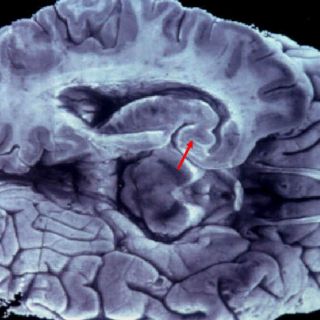

MADRID, ESPAÑA (09/MAY/2012).- Un equipo del Instituto de Investigación Biomédica (IRB Barcelona), encabezado por el científico Eduardo Soriano, identificó una nueva familia de seis genes cuya función es regular el movimiento y posición de las mitocondrias en las neuronas.

Los científicos comprobaron a través de análisis genómicos comparados que estos genes se encuentran sólo en los mamíferos más evolucionados, los denominados euterios, con fecundación y desarrollo internos.

"El hallazgo indica la importancia de la biología de las mitocondrias. Cuando el cerebro evolucionó en volumen, función y estructura, el proceso de transporte de mitocondrias también se hizo más complejo y probablemente requirió mecanismos adicionales de control", explicó Soriano.

Resaltó que dado el origen del clúster génico, en la transición entre mamíferos primitivos, como los marsupiales (canguros) y el resto de mamíferos placentarios, es tentador lanzar la hipótesis de que su origen esté ligado al incremento en complejidad del córtex cerebral en el linaje que lleva hasta el hombre.

Subrayó que para que el cerebro funcione correctamente requiere una gran cantidad de energía, pero esta energía tiene que estar exquisitamente distribuida a lo largo y ancho de las neuronas, unas células que tienen ramificaciones que pueden llegar a ser de decenas de centímetros, desde el cerebro hasta las extremidades.